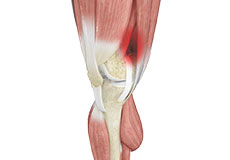

Muscles of the Knee

There are two major muscles in the knee - the quadriceps and the hamstrings, which enable movement of the knee joint. The quadriceps muscles are located in front of the thigh. When the quadriceps muscles contract, the knee straightens. The hamstrings are located at the back of the thigh. When the hamstring muscles contract, the knee bends.